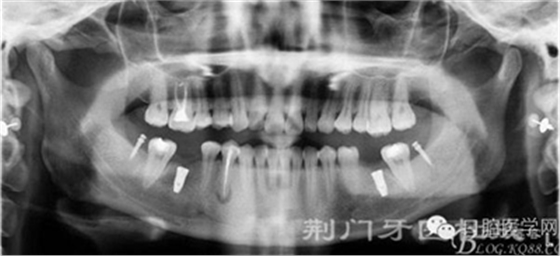

檢查:16齲壞穿髓,探(-)叩(+++),無松動(dòng),36 46 缺失,37 47 近中傾斜嚴(yán)重,44畸形中央尖牙體變色,叩(+),溫度測(cè)試無反應(yīng) ,18 28 38 48 萌出牙體偏頰

X線片